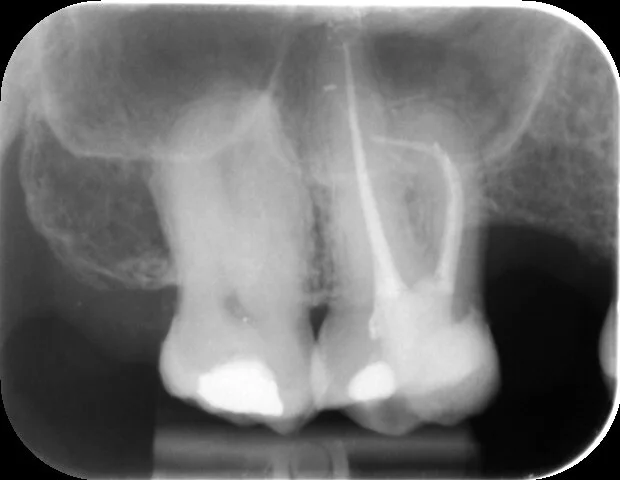

The fully obturated canals reveal the true nature of that extreme curvature in the mesio-buccal canal